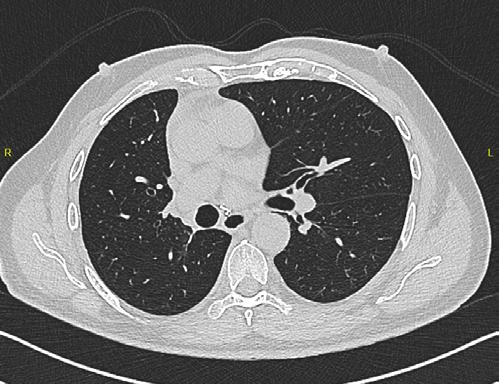

La TC de baja dosis, es la modalidad de imagen más utilizada como método de escrutinio para la detección de lesiones pulmonares, es un estudio rápido, que no requiere preparación previa. ESCANERS DE UN PACIENTE CON

Figura 1-4. Estudio de tomografía simple de tórax, con reconstrucción volumétrica, multiplanares con ventana para pulmón y en mediastino (, en donde se observa el nódulo pulmonar sólido de bordes lobulados hipodensos.

Se presente al caso de un masculino de 80 años de edad que acude por presentar tos en estudio de 3 meses de evolución, sin datos de fatiga, como antecedente de importancia tabaquismo por lapso de 40 años a razón de 1 cajetilla y media diaria (exposición de 60 paquetes año), actualmente suspendido.

Se le realiza estudio de tomografía simple de tórax en donde se encontró en el segmento anterior del lóbulo inferior derecho nódulo sólido, con diámetro de 22mm, volumen de 2.9ml, condiciona disminución del bronquio segmentario, con secreciones endoluminales distales, de acuerdo a la clasificación de LUNG RADS con categoría 4B, alta sospecha de malignidad. Sin evidencia de lesiones nodulares en el resto del parénquima.

Posteriormente, se realiza estudio de PET-CT con 18FDG , con hallazgos de metabolismo asociado y SULmax de 2.0, se recomienda realizar biopsia.

Se realiza cirugía con lobectomía inferior derecha, con resultado histopatológico de tumor carcinoide atípico, se realiza seguimiento con tomografía simple de tórax sin complicaciones en el lecho quirúrgico.

Figura 5. Estudio de PET-CT con FDG que muestra hipercaptación del radiofármaco en el nódulo pulmonar, lo que traduce en metabolismo aumentado.

Figura 6. Estudio de seguimiento postlobotomía.

El sistema LUNG RADS para la evaluación de nódulos pulmonares observados en TC de tórax de baja dosis, establece categorías del 0 al 4, dividiendo ésta última en 4A, 4B y 4X, en el caso de los nódulos 4B se establece que son nódulos sólidos con diámetro de 15 mm en el estudio basal o nódulos subsólidos con porción sólida de 8 mm, en la versión actualizada del 2022, se agregan quistes aéreos atípicos con engrosamiento mural o componente nodular mural. La recomendación para esta categoría es la realización de PET CT y/o toma de biopsia.